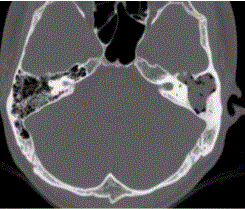

问题 患者男,25岁,右耳流脓液、听力下降5年。查体:右侧鼓膜穿孔,传导性耳聋,CT检查如下图。 临床拟诊为

选项 A.慢性中耳乳突炎伴胆脂瘤形成 B.急性化脓性中耳炎 C.神经鞘膜瘤 D.组织细胞增生症 E.鼓室球瘤 F.外耳道胆脂瘤

答案 A